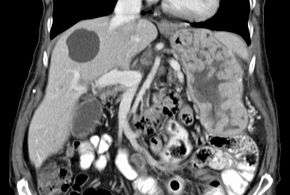

| Gross specimen of biopsy of stomach in Ménétrier disease. In this case, the substantial pit hyperplasia makes the large rugal folds appear to be covered by myriad polyps resembling hyperplastic polyps. The muscularis propria is the folded structure at the bottom center. | |

With Ménétrier disease, the stomach is characterized by large, tortuous gastric folds in the fundus and body of the stomach, with antrum generally spared, giving the mucosa a cobblestone or cerebriform (brain-like) appearance.[5] Histologically, the most characteristic feature is massive foveolar hyperplasia (hyperplasia of surface and glandular mucous cells).[3] The glands are elongated with a corkscrew-like appearance and cystic dilation is common. Inflammation is usually only modest, although some cases show marked intraepithelial lymphocytosis. Diffuse or patchy glandular atrophy, evident as hypoplasia of parietal and chief cells, is typical.[4]